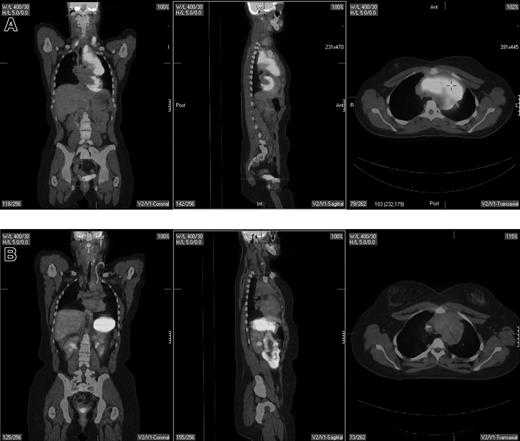

The clearest role for PET is in restaging patients following the completion of therapy.18,50-55 Restaging PET scanning is performed either for a final response assessment, typically within 6 to 8 weeks of therapy conclusion, or to determine the extent of known or suspected recurrence anytime after therapy. PET is more accurate than CT in this setting (Figure 2), largely related to its superiority in distinguishing between viable tumor and necrosis or fibrosis in residual mass(es). Jerusalem et al50 prospectively evaluated 54 patients with NHL (n = 35) and HL (n = 19), 24 with residual CT masses. All 6 patients with a positive PET scan relapsed compared with 5 (26%) of 19 CT+/PET− patients and 3 (10%) of 29 CT−/PET− patients. Eight of 48 patients relapsed despite a negative PET scan, suggesting the possibility of either residual disease below the resolution of the scanner or a false-negative result. Zinzani et al51 reported that all 13 aggressive NHL and HL patients with CT+PET+ residual abdominal masses relapsed (11 within 8 months) compared with only 1 of 24 CT+/PET− patients, who relapsed within 4 months at a previously involved site of disease. Spaepen et al53 reported on 93 patients with NHL; 56 of 67 patients with a normal PET scan after first-line chemotherapy remained in a complete remission (CR) at a median follow up of 653 days, compared with a relapse in all 26 patients with an abnormal PET scan occurring at a median of 73 days. In a retrospective analysis, Spaepen et al54 reported that 50 of 55 patients with a negative PET scan after completion of first-line treatment for HL remained in a complete remission at a median follow up of 955 days compared with all 5 patients with persistent abnormal FDG uptake who relapsed (median progression-free survival [PFS], 296 days).

Pretherapy and posttherapy fused PET/CT images in a 17-year-old female patient with nodular sclerosis Hodgkin disease. The pretherapy images (top) showed bilateral supraclavicular, anterior mediastinal, and left hilar lymphadenopathy by both PET and CT. Posttherapy PET/CT performed 4 weeks following completion of 6 cycles of ABVD (doxorubicin, bleomycin, vinblastine, dacarbazine) showed resolution of disease in the supraclavicular and left hilar region but continued to show a residual 6.2 × 3.4-cm mass in the anterior mediastinum that was PET negative. Multiple biopsies of the mass showed only fibrous tissue with no evidence of lymphoma. The patient is currently without evidence of disease after 4 years of follow-up.

The studies by Jerusalem et al50 and Spaepen et al53,54 used non–attenuation-corrected PET images, where mild FDG-PET uptake, particularly in deep-seated lymph nodes or nodal masses, may have gone undetected, since they fail to correct for absorption of photons through body tissues to obtain a true measure of accumulated activity. Weihrauch et al52 and Juweid et al,18 on the other hand, used currently standard attenuation-corrected PET to evaluate the predictive value of PET in HL and aggressive NHL, respectively. In a prospective series including 29 patients Weihrauch et al52 showed that 16 of 19 HL patients with PET-negative mediastinal tumor after first-line therapy remained in remission at a median follow up of 28 months, while 6 of 10 PET-positive patients progressed. Thus, the positive predictive value (PPV) of PET (the ability of a positive PET scan to predict persistent disease or future relapse) in this study was only 60%, while the negative predictive value (NPV) (the ability of a negative PET scan to exclude persistent disease or future relapse) was 84%. Juweid et al18 found in a retrospective evaluation of 54 patients with aggressive NHL a PPV of 74% and a NPV of 83% for attenuation-corrected PET scans.

In general, PET has a consistently high NPV averaging about 85% across studies including patients with HL and/or diffuse large B-cell NHL.18,50-55 The approximately 15% false-negative rate with PET is mostly related to its inability to detect microscopic disease resulting in future relapse. The PPV of PET is generally lower and considerably more variable averaging about 70% to 80%, with generally lower average values in patients with HL (∼ 65%) compared with NHL (∼ 85%).18,50-54 The reported generally lower PPV of PET in Hodgkin lymphoma compared with aggressive NHL is likely related to the substantial fraction of Hodgkin lymphoma patients who received radiation therapy, either alone or combined with chemotherapy, prior to undergoing PET.52 Postradiation inflammatory changes can lead to a false-positive PET scan. Still, the PPV of PET is substantially higher than CT, which has a reported PPV in patients with aggressive NHL of approximately 40% to 50% and in HL of only approximately 20%. The NPV of PET is similar to that of CT resulting in a considerably higher accuracy of PET for response assessment compared with CT (approximately 80% vs 50%).